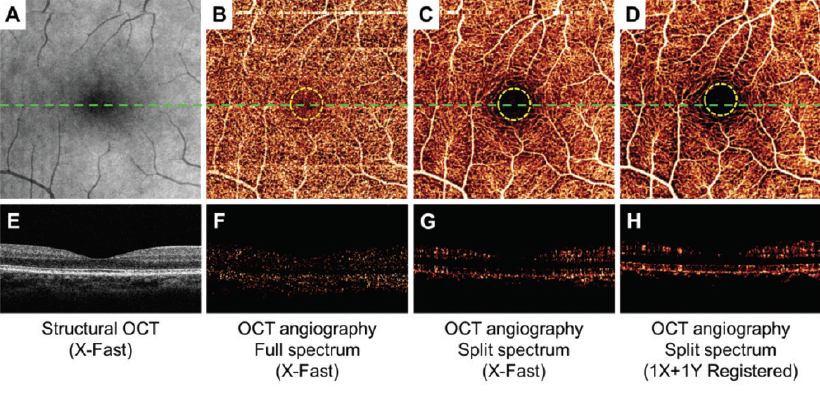

Figure 1. En face maximum decorrelation projections of retinal circulation show less noise inside the FAZ (within yellow dotted circles) and more continuous perifoveal vascular networks using the SSADA algorithm (C and D) compared with standard full-spectrum algorithm (B). The cross-sectional angiograms (scanned across the green dashed line in B, C, and D) show more clearly delineated retinal vessels and less noise using the SSADA algorithm (G and H) than the standard full-spectrum algorithm (F).

David Huang, MD, PhD, created the split-spectrum amplitude-decorrelation angiography (SSADA) algorithm,1 which detects motion in blood vessels by measuring variations in the reflected OCT signal amplitude between consecutive cross-sectional scans and then processes it to enhance flow detection and reject axial bulk motion noise. The SSADA algorithm splits the OCT image into different spectral bands, thereby increasing the number of usable image frames and shortening the scan acquisition process. Compared with full-spectrum methods, SSADA improves the signal-to-noise (SNR) ratio to provide clean and continuous imaging of the microvascular network with less noise inside the foveal avascular zone (FAZ) (Figure 1).